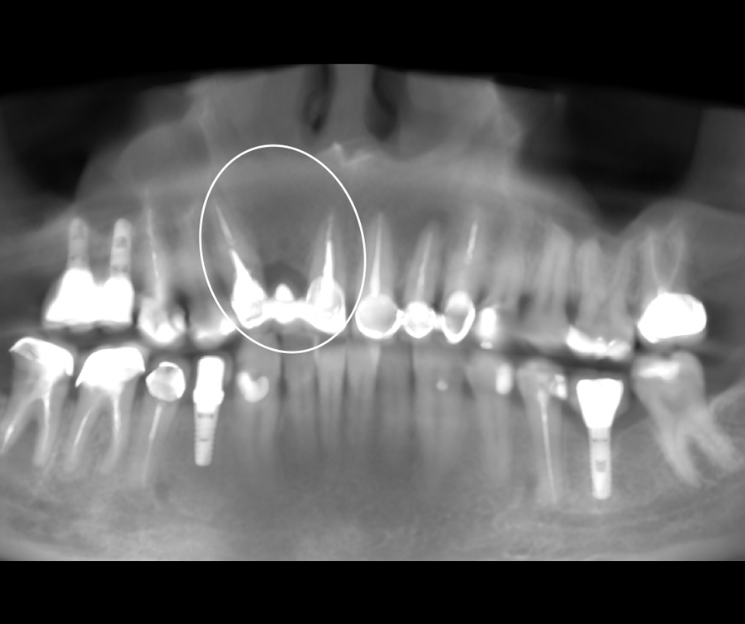

Extracción de piezas 21, 22 y 23 con infección activa

Paciente con infecciones de origen dental que comprometían severamente el hueso alveolar en la zona anterior superior. Se realizó la extracción de los dientes 21, 22 y 23, y se optó por una rehabilitación inmediata mediante implantes córticobasales.

Esta combinación permitió anclar los implantes en hueso cortical, que mantiene su estabilidad incluso en presencia de procesos infecciosos en el hueso alveolar. El resultado: rehabilitación funcional y estética el mismo día de la cirugía.